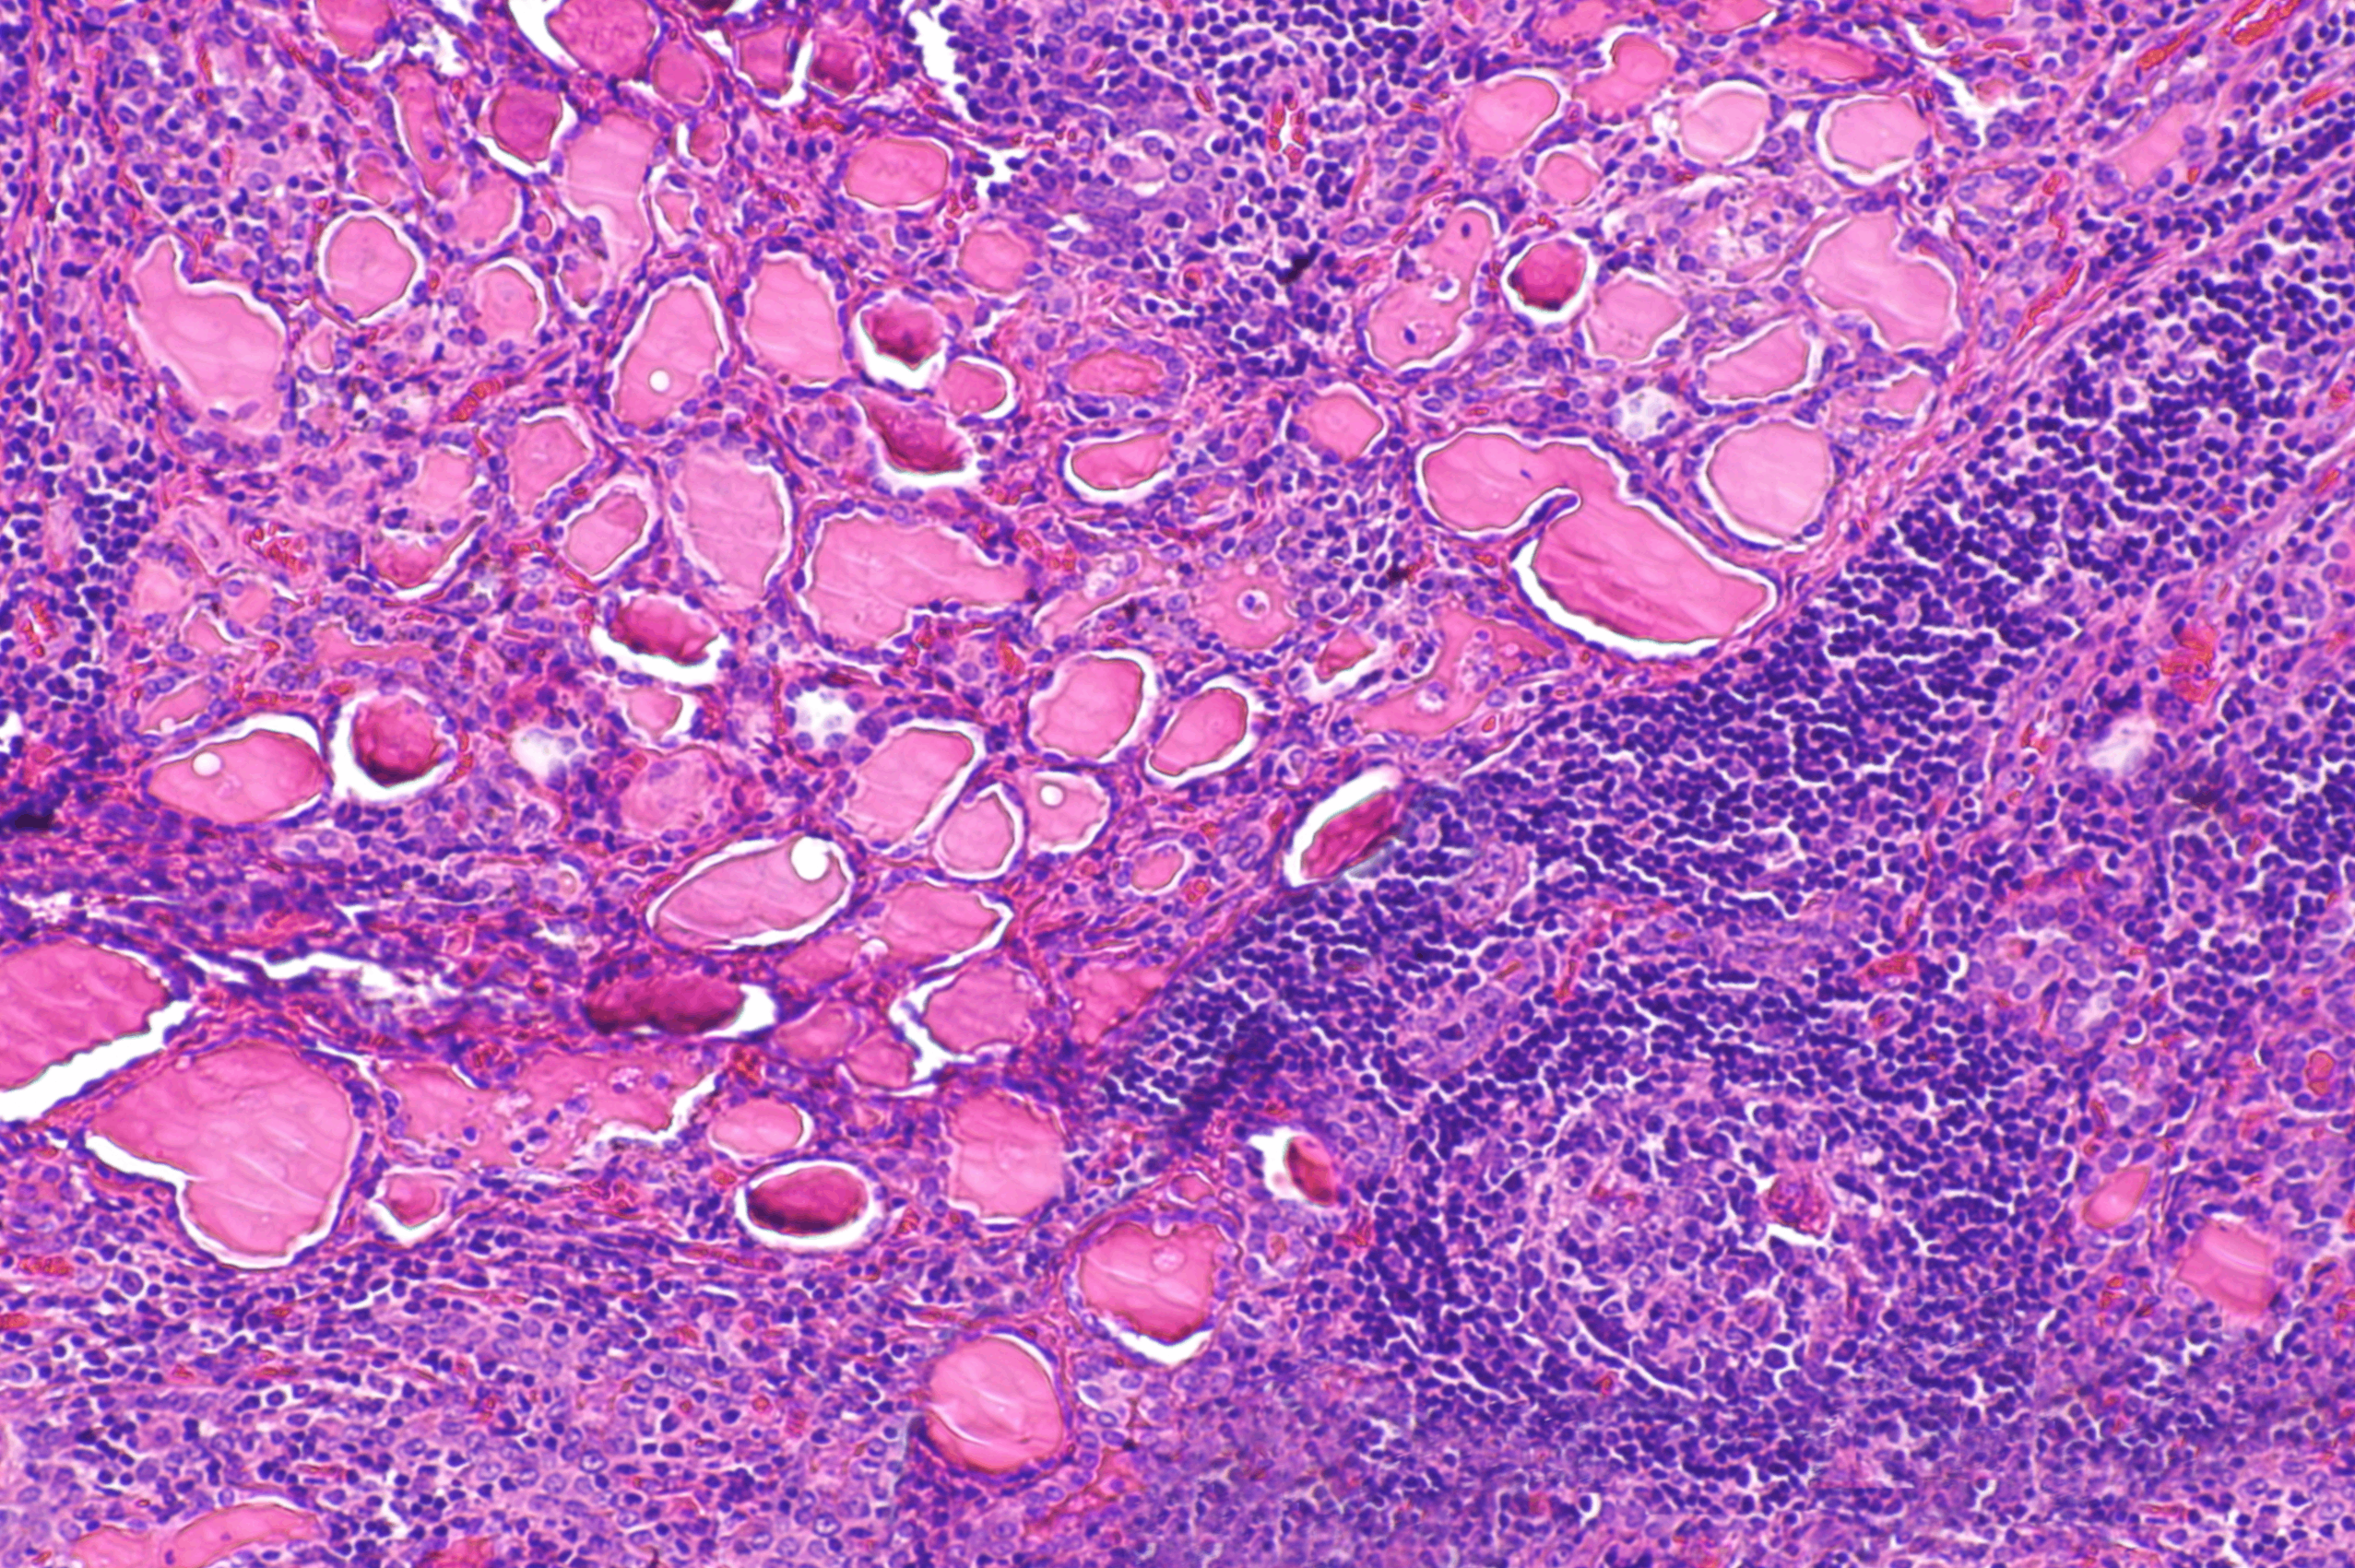

(4) 조직학적 소견

• 갑상선은 대칭적으로 비대되어 있으며 이는 갑상선 여포 상피세포(thyroid follicular epithelial cell)의 미만성 비대 및 과형성(hyperplasia)에 기인함

여포 상피세포는 길고 조밀하게 밀집되어 있으며, 이러한 세포 밀집은 유두(papillae) 형성으로 이어짐. 해당 구조는 여포 내강으로 돌출되고 colloid을 침범하거나 때로는 여포를 거의 채우기도 함. 단, 유두암의 유두와 달리 fibrovascular core는 없음

• 갑상선의 간질에는 림프구 침윤이 관찰되며, 주로 T세포로 구성되고, 일부 B세포와 형질세포도 산재해 있음. 또한, germinal center이 형성되어 있는 경우도 있음.

Histopathology of Graves' Disease, Wikipedia Commons